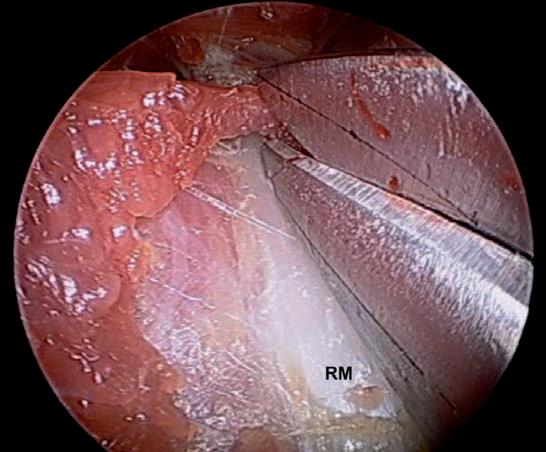

Al seccionar la fascia estamos disminuyendo la tracción de ésta sobre su inserción en el epicóndilo, por lo que podemos considerarlo, de forma indirecta, como el tratamiento de una eventual epicondilitis si coexiste con este cuadro clínico. Siguiendo estas indicaciones, nos encontraremos aproximadamente a la mitad del canal radial. A continuación se realiza una disección roma del fascículo superficial del supinador, que aparece como el suelo del canal donde estamos trabajando, hasta identificar la rama motora del radial (RMR) que, si se han realizado correctamente los marcajes cutáneos, debe aparecer en el mismo plano de la disección (Fig. 22). Para ello usamos una tijera de Metzembaum curva; este paso es crítico en esta técnica, porque al realizar una búsqueda del nervio a través del músculo a ciegas, podemos lesionar el nervio antes de identificarlo si no se ha realizado una disección extremadamente cautelosa (Fig. 23). Una vez identificada la RMR proseguimos con la disección del fascículo del supinador en dirección proximal hasta la arcada de Fröhse, que seccionaremos. Procedemos a la disección en sentido proximal de la RMR hasta identificar los ramos vasculares que la cruzan (arteria comunicante radial conocida en la literatura como Leash of Henry). Si no se aprecian evidencias de compresión del nervio a este nivel, se conservarán dichos vasos y se concluirá́ la disección en sentido proximal, retirando con cuidado el instrumental a la vez que se comprueba visualmente que el nervio está completamente liberado (Fig. 24). Seguidamente se procede con la liberación en sentido distal. Ésta es bastante más difícil que la anterior, puesto que la posición del cirujano es más incómoda y las ramas distales del nervio interóseo posterior son extremadamente delgadas y es fácil lesionarlas incluso con la introducción del separador.

Fig. 23: Detalle de la disección del fascículo superficial para exponer hasta exponer la rama motora del radial en el intervalo entre los fascículos superficial y profundo del supinador. RM Rama motora.

Fig. 24: Aspecto del nervio completamente liberado. Los asteriscos (*) marcan los márgenes libres de la arcada de Fröhse que se ha seccionado completamente. RM Rama motora.